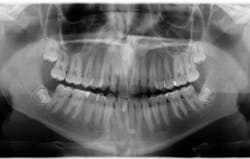

Image of a radiograph with evident loss of enamel in mandibular first molar.